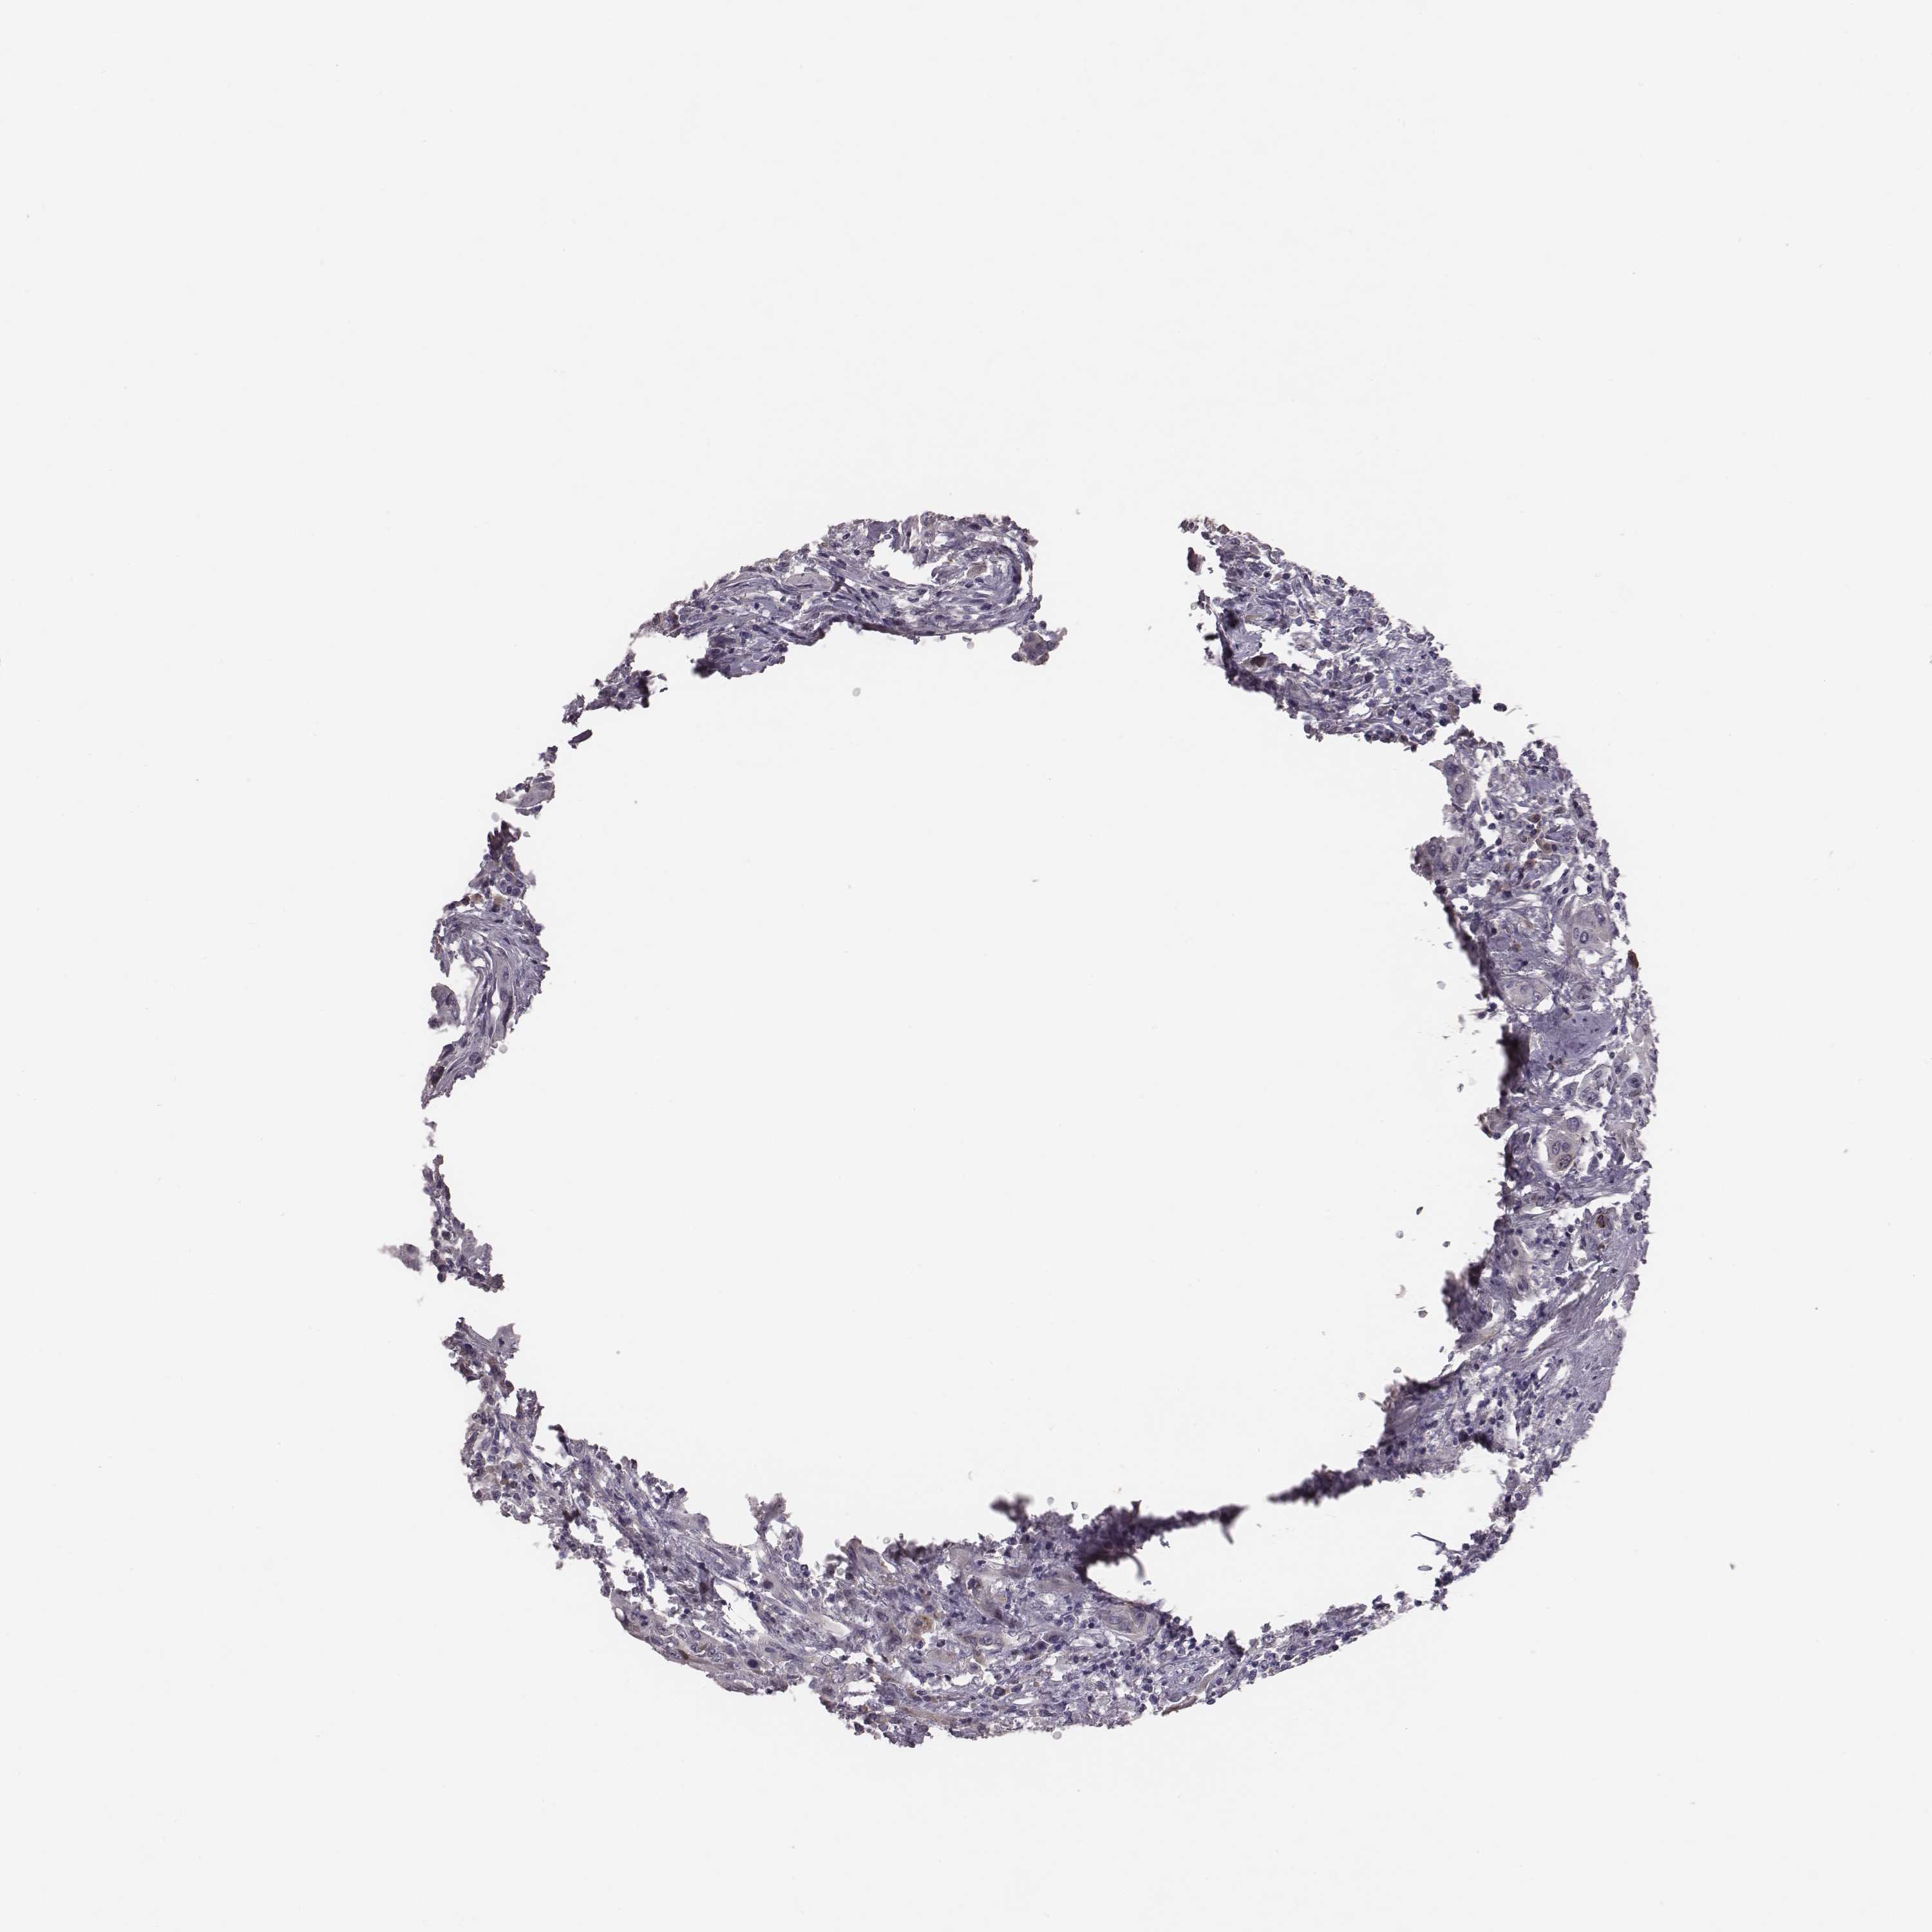

UROTHELIAL CANCER - Protein expressioni

A mouse-over function shows sample information and annotation data. Click on an image to view it in a full screen mode. Samples can be filtered based on level of antibody staining by selecting one or several of the following categories: high, medium, low and not detected. The assay and annotation is described here.

Note that samples used for immunohistochemistry by the Human Protein Atlas do not correspond to samples in the TCGA dataset.

Antibody stainingi

Antibody staining in the annotated cell types in the current human tissue is reported as not detected, low, medium, or high, based on conventional immunohistochemistry profiling in selected tissues. This score is based on the combination of the staining intensity and fraction of stained cells.

Each image is clickable and will lead to virtual microscopy that enables deeper exploration of all samples and also displays staining intensity scores, fraction scores and subcellular localization as well as patient and tissue information for each sample.

Antibody HPA073141

Staining

High

Medium

Low

Not detected

Intensity

Strong

Moderate

Weak

Negative

Quantity

>75%

75%-25%

<25%

None

Location

Nuclear

Cytoplasmic/membranous

Cytoplasmic/membranous,nuclear

Urothelial carcinoma, High grade

Urothelial carcinoma, NOS

Urothelial carcinoma, Low grade